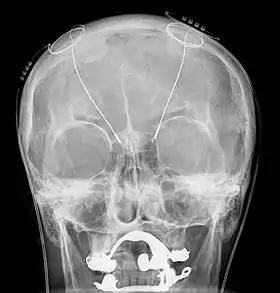

![]() مجسات التحفيز العميق للدماغ كما تظهر في صورة بالأشعة السينية (المنطقة البيضاء المحيطة بالفكين العلوي والسفلي يظهران طقم الأسنان المعدني والذي لا علاقة له بجهاز التحفيز العميق) | |

بعدها يتم تركيب الأقطاب الكهربائية الدائمة وتثبت في الجمجمة، وبعد هذه المرحلة يتم عمل أشعة لتحديد موقع الأقطاب داخل الدماغ وأي تغيرات بعد العمل الجراحي.